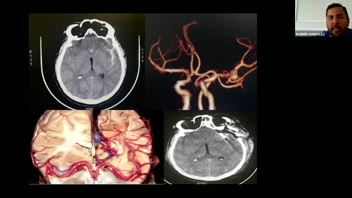

Endovascular Management of Giant Intracrianal Aneurysms; Dr. Angel Ferrario.

Management of Giant Cerebral Aneurysms